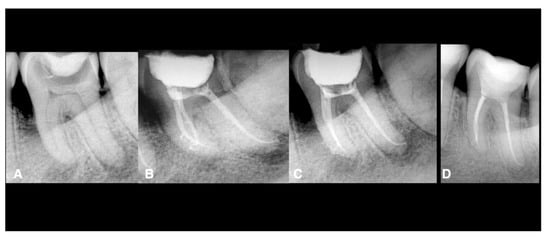

| All data Male: 55 Female: 35 Age: all the patients were between 20 and 45 years. Oral hygiene: 65 patients had good hygiene. Tobacco use: 10 patients used it. Teeth: 20 maxillary molars, 40 mandibular molars, 30 maxillary premolars. Intraoperative data collection Twenty teeth had sealer extrusions. The working length was respected in all teeth. Postoperative data collection Post-treatment symptoms were assessed two days after the treatment using a visual analogue scale (VAS; 0 and 10) Thirteen maxillary molars: 2 Seven maxillary molars: 1 Five mandibular molars: 4 Eighteen mandibular molars: 3 Ten mandibular molars: 2 Seven mandibular molars: 1 Sixteen maxillary premolars: 2 Twelve maxillary premolars: 1 Two maxillary premolars: 3 Total number: 90 teeth Two patients (2 teeth) did not come for the follow-up. Of the 88 teeth, 84 (95%) were healed, and four (5%) failed. Four teeth failed: 2 maxillary premolars and two mandibular molars (these teeth did not have sealer extrusion). One maxillary premolar failed with vertical root fracture. |

| Maxillary molars | 20 | 7 (35.0) | 13 (65.0) | 0 (0.0) | 0 (0.0) | 19 (95.0) | 6 (30.0) | 0 (0.0) | 0 (0.0) |

| Mandibular molars | 40 | 7 (17.5) | 10 (25.0) | 18 (45.0) | 5 (12.5) | 40 (100.0) | 10 (25.0) | 2 (5.0) | 2 (5.0) |